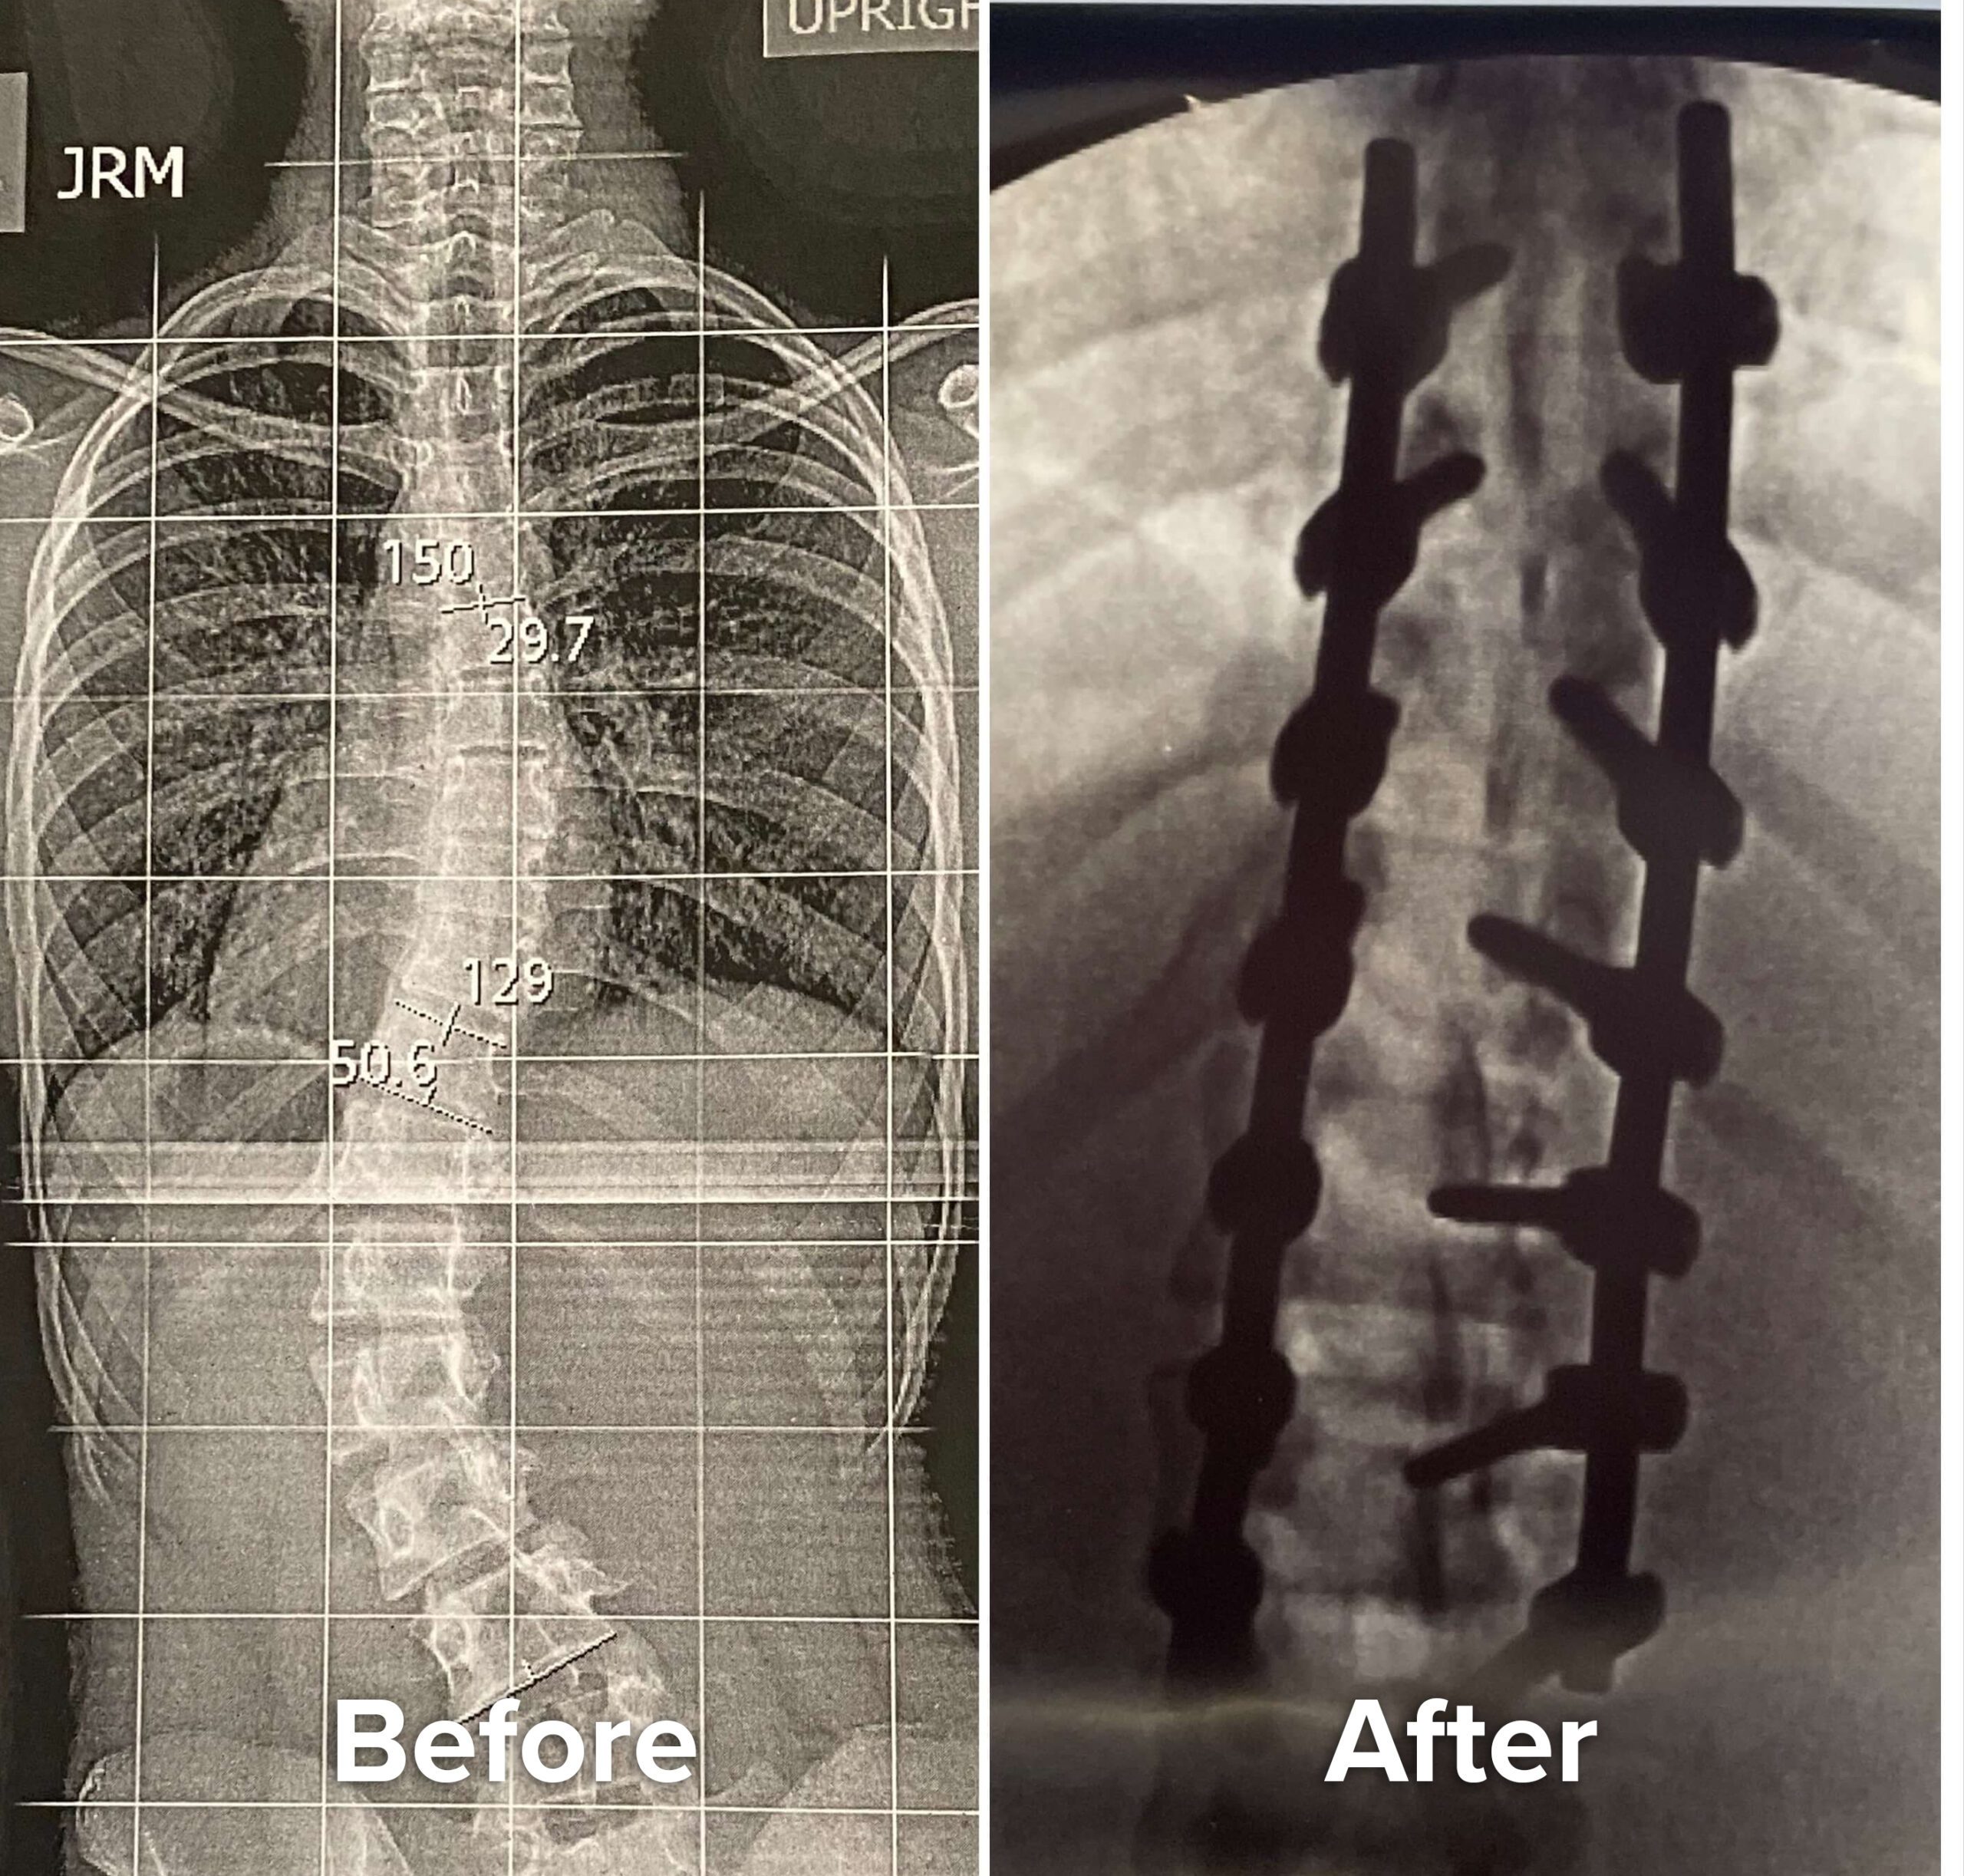

Everything took a turn for the worse when in 8th grade I went for my routine checkup and found out the brace hadn’t worked. My spine had a 50 degree curve in the lumbar region and a 30 degree curve at the top. Surgery was inevitable. My head started to spin and my hands started to tremble as I felt the anxiety start to arise. Surgery was scheduled the summer before my freshman year to ensure I had enough time to recover before the school year because of the 6 month recovery time.

Ultimately, the surgery was unavoidable and on July 23, 2022 I underwent the spinal fusion procedure. I had two titanium rods inserted in my back fusing seven vertebrate in my spine. The surgery included 5 grueling days in the ICU and months of recovery. I was unable to do anything on my own for weeks. I could not walk on my own, bathe or even use the rest room without assistance. Everything was a struggle.